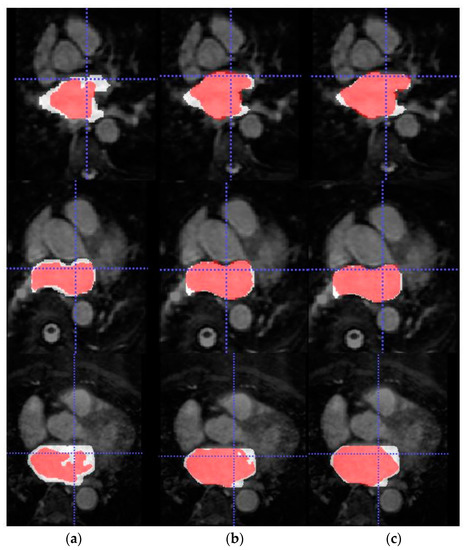

To further assess the evaluation performance of each model, qualitative results of the segmentation predictions were obtained.

Figure 6 shows the axial view of predictions obtained for three representative testing patients (and slices) of Database 3 with the different trained models for RA segmentation.

Due to the absence of previous works that employ Database 3 solely as an external validation dataset, we are not able to compare the generalization ability of our proposed model. On the other hand, a visual representation of the increased performance of the models with SDA can be seen in Figure 5 and Figure 6 for LA and RA segmentation tasks, respectively. As we can observe, the blood pool prediction segmentation of the LA and RA performs best in the SDA model.

Figure 6. From left to right, axial slice of RA segmentations in networks w/o SDA (left) and w-SDA (right) for 3 patients (ac).